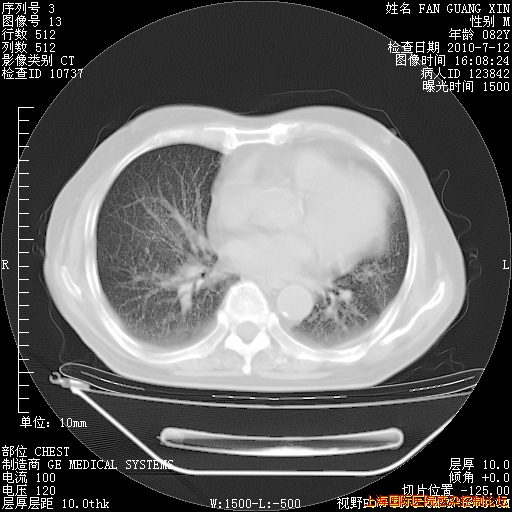

今天复查CT

今天CT

整整相隔30天的肺部CT好像有所好转啊。甲强龙减量第3天,需要观察体温。

海管,自昨日你和我通完话后,不知您岳父消化道症状有无缓解?体温怎样?阅读7.12日胸部ct,个人认为目前激素治疗是有效的,甲强龙减量是适宜的。因在抗痨治疗,需密切观察肝功、肾功能和血常规。不过,老年、长期住院和大量使用激素,很担心菌群失调发生